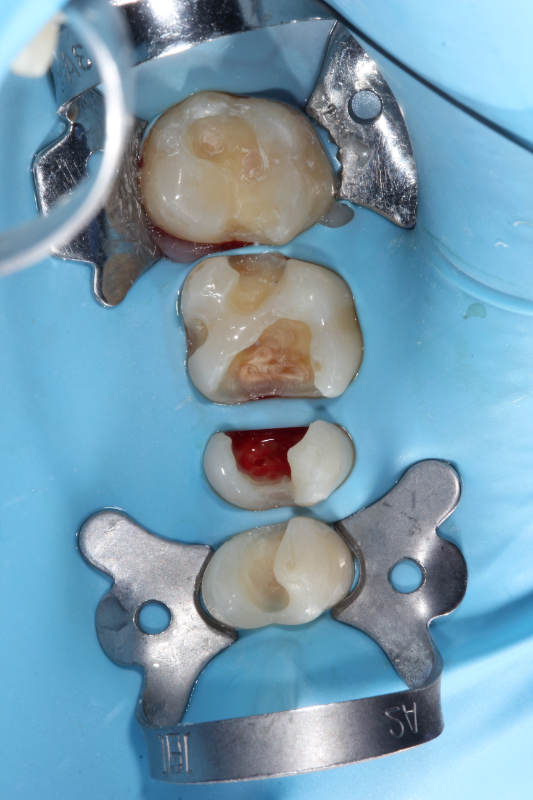

- Precizní čištění kanálků — pod mikroskopem, abychom nic nepřehlédli.

- Dezinfekce — důkladné odstranění infekce.

- Zaplnění kanálků — hermetické utěsnění speciálním materiálem.

- Obnova zubu — výplň nebo korunka, aby byl zub opět pevný.